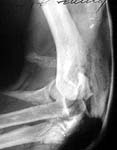

Regarding this patient with distal humerus fracture, proximal ulna fracture , open with elbow joint subluxation. The ulna is extremely comminuted but plating can be effective in such a situation as illustrated in the previous reply. I wonder if the articulated ring fixator or Oganesyan would be a good option in your setting.

As a small note, the threads of the lag screw in the distal humerus may cross the fracture line and this kind of single screw fixation can be tenuous, even if supplemented by external fixation.